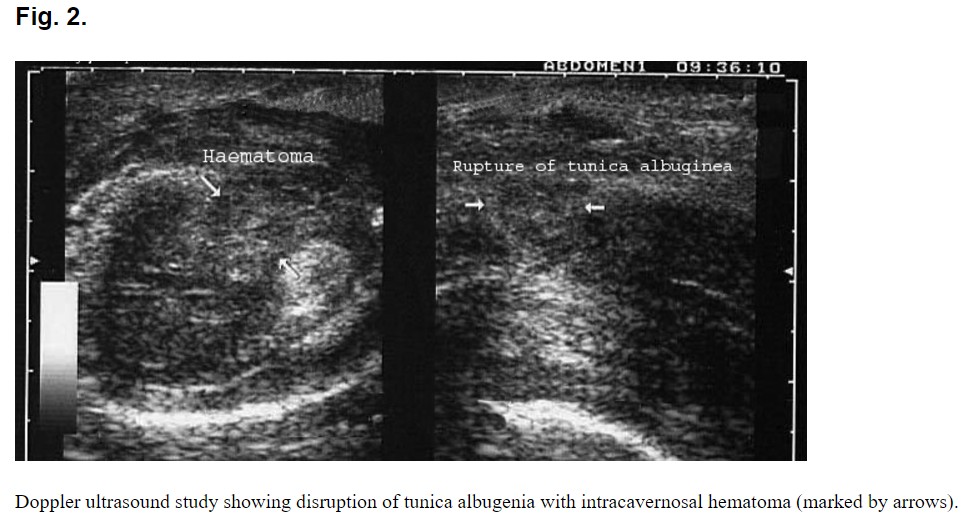

La pose más peligrosa para que suceda este tipo de fractura es cuando la mujer se encuentre encima del hombre, usualmente el accidente se produce cuando el miembro choca con la pelvis de su pareja, rompiendo la túnica albugínea y extravasando gran cantidad de sangre que forma un hematoma importante.

«El diagnóstico es clínico, sin embargo la ayuda de imágenes (ecografía) es fundamental para el planeamiento quirúrgico.»